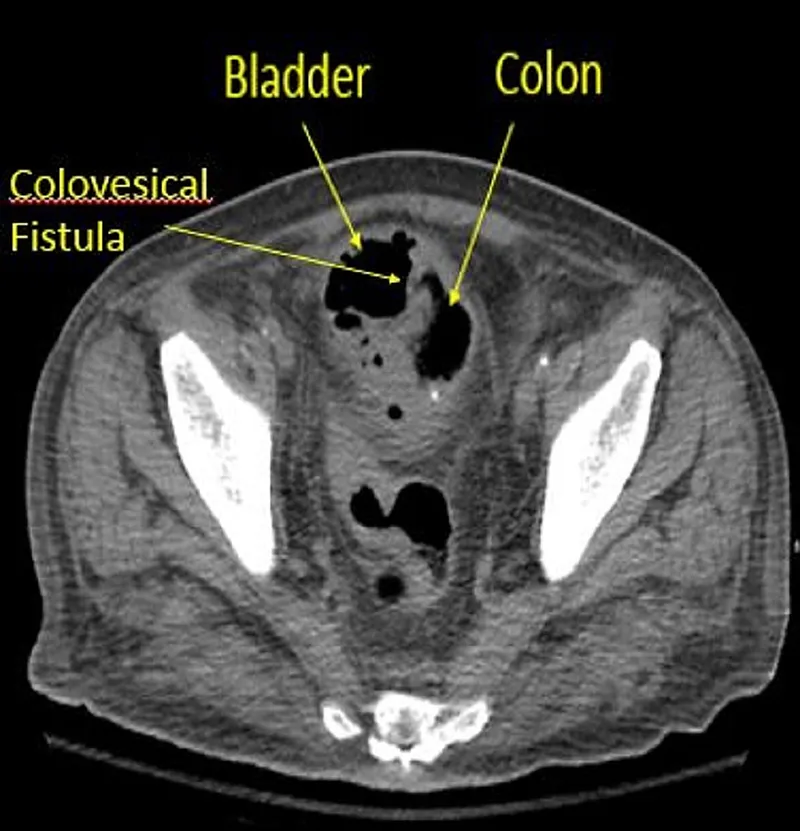

⭐ The most common fistula in diverticulitis is a colovesical fistula, presenting with pneumaturia (air in urine), fecaluria, and recurrent UTIs.

- Fistula: Colovesical is classic → pneumaturia, fecaluria. Colovaginal also possible.

⭐ While most diverticular bleeding stops spontaneously (>75%), colovesical fistula is the most common fistula type associated with diverticulitis.